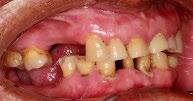

En los estudios intraorales, las fotografías iniciales muestran clase I canina y molar bilateral, mordida anterior abierta, apiñamiento leve superior e inferior, y líneas medias dentales

desviadas. En las Figuras 4, 5 y 6 se observa la forma de las arcadas superior e inferior.

Figura 4. Lateral derecha.

Figura 5. Intraoral de frente e izquierda.